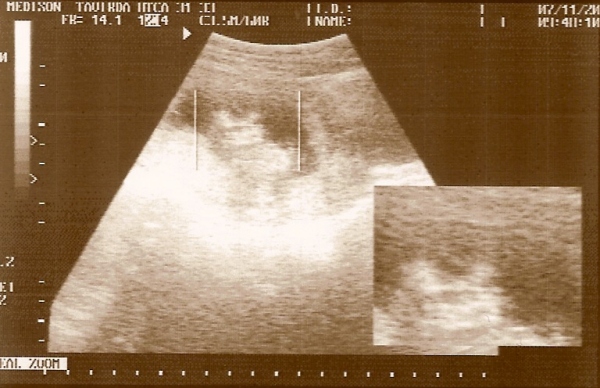

a kis arcocskája (nagyon rossz a kép)

a kis arcocskája (nagyon rossz a kép)